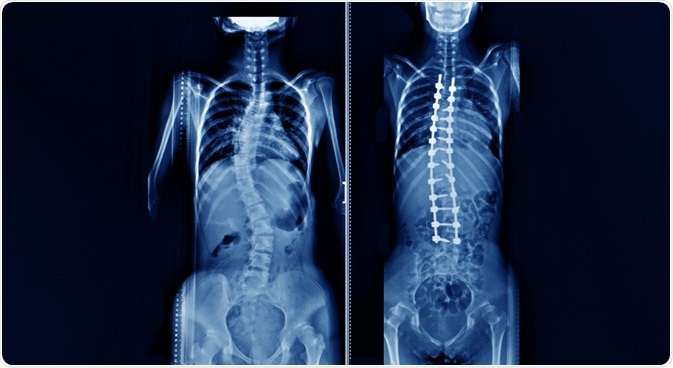

scoliosisWhole spine x-ray shwoing a patient with adolescent idiopathic scoliosis before and after correction deformity surgery. Image Credit: Yok_onepiece / Shutterstock.com

The treatment of scoliosis associated with Marfan syndrome depends on the extent of the curvature of the spine. In mild cases, monitoring for signs of worsening is sufficient, and a back brace is required for patients to prevent further development of symptoms in some cases. For more severe cases of scoliosis, surgical intervention may be required to straighten the spine.